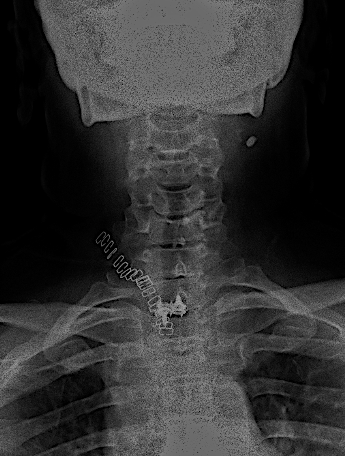

RX AP control postoperatoria.

Obsérvese, en la imagen anterior, la incisión usada en relación con la prótesis. No fue necesario realizar ninguna esternotomía (aunque el cirujano torácico estaba avisado). Para mejorar la visión sí que se resecó parte del platillo inferoanterior de Th1.

La caja atornillada no planteó tantas dificultades como la descompresión.

Difícilmente se aprecia la prótesis

Copia con marcaje de los tornillos de la misma

En las RX lateral de control no se aprecia bien la caja atornillada, sin embargo, la paciente mejoró la clínica álgica y mostró recuperación funcional en MSD en los controles, por lo que decidí esperar a los 6 meses para la RM cervical.